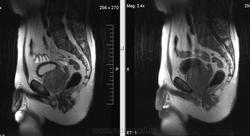

Метастазы рака простаты, кроме измений в позвонках видна сама первичная опухоль и лимфатические узлы (общий и наружный подвздошные слева, ещё один в левой подвздошной ямке).

После добавления томограмм исследования органов малого таза картина стала ещё печальнее...

Да, запустил пациент. До этого были проблемы с мочеиспусканием, рези, болезненность. Лечился самостоятельно от простатита, отмечал временное улучшение.